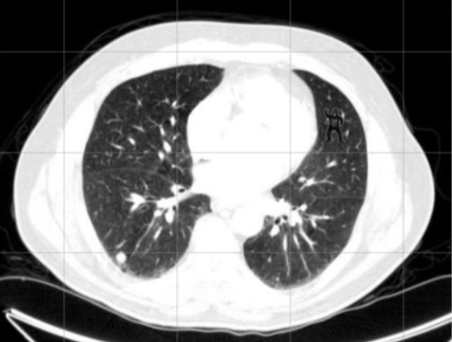

Este efecto de la ceguera inatencional resulta de lo más divertido cuando experimentamos con un tipo disfrazado de gorila, pero puede impactarnos cuando lo trasladamos a decisiones en el mundo real. Por ejemplo, al trabajo cotidiano de los radiólogos4. En un experimento en 2013 de Drew y colaboradores, los investigadores pidieron a 24 radiólogos que escanearan diferentes imágenes con el objetivo de localizar en ellas nódulos cancerígenos.

Lo que no sabían los especialistas es que estas imágenes escondían también la figura de un pequeño gorila. Veinte de ellos, el 83%, no llegaron a detectar al gorila. Fueron ciegos a lo que no atendieron.

Imagen de Drew y colaboradores (2013)5